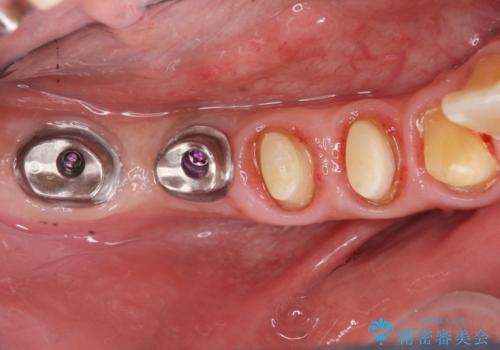

検査の結果、残すことの難しい歯をインプラントに置き換え、残すことのできる歯は虫歯の徹底的な除去後にセラミック治療を行っていくこととしました。

- 125万円(インプラント×2・チタンカスタムアバットメント×2・ジルコニアクラウン×4・仮歯×4)費用は治療当時の料金となります